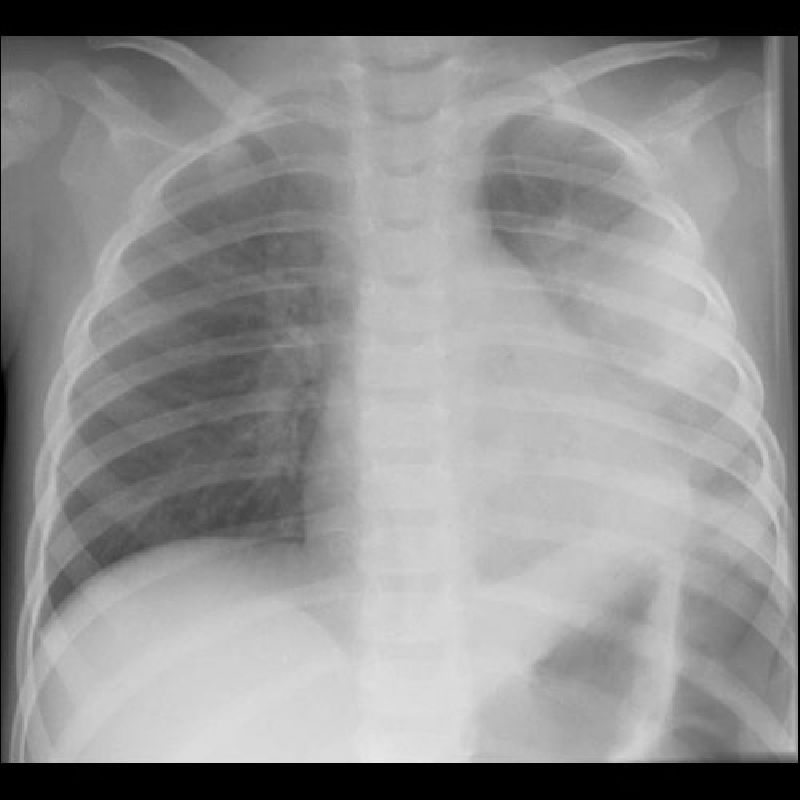

Mii de infectii acute ale cailor respiratorii

Specialistii Autoritatii de Sanatate Publica Judeteana (ASPJ) Constanta au continuat monitorizarea afectiunilor sezonului rece si in aceasta perioada. Potrivit directorului adjunct al ASPJ, dr. Mihaela Dinisov, in cadrul sistemului de supraveghere a infectiilor respiratorii, in saptamana 8 – 14 decembrie 2008, au fost semnalate mii de infectii acute ale cailor […]